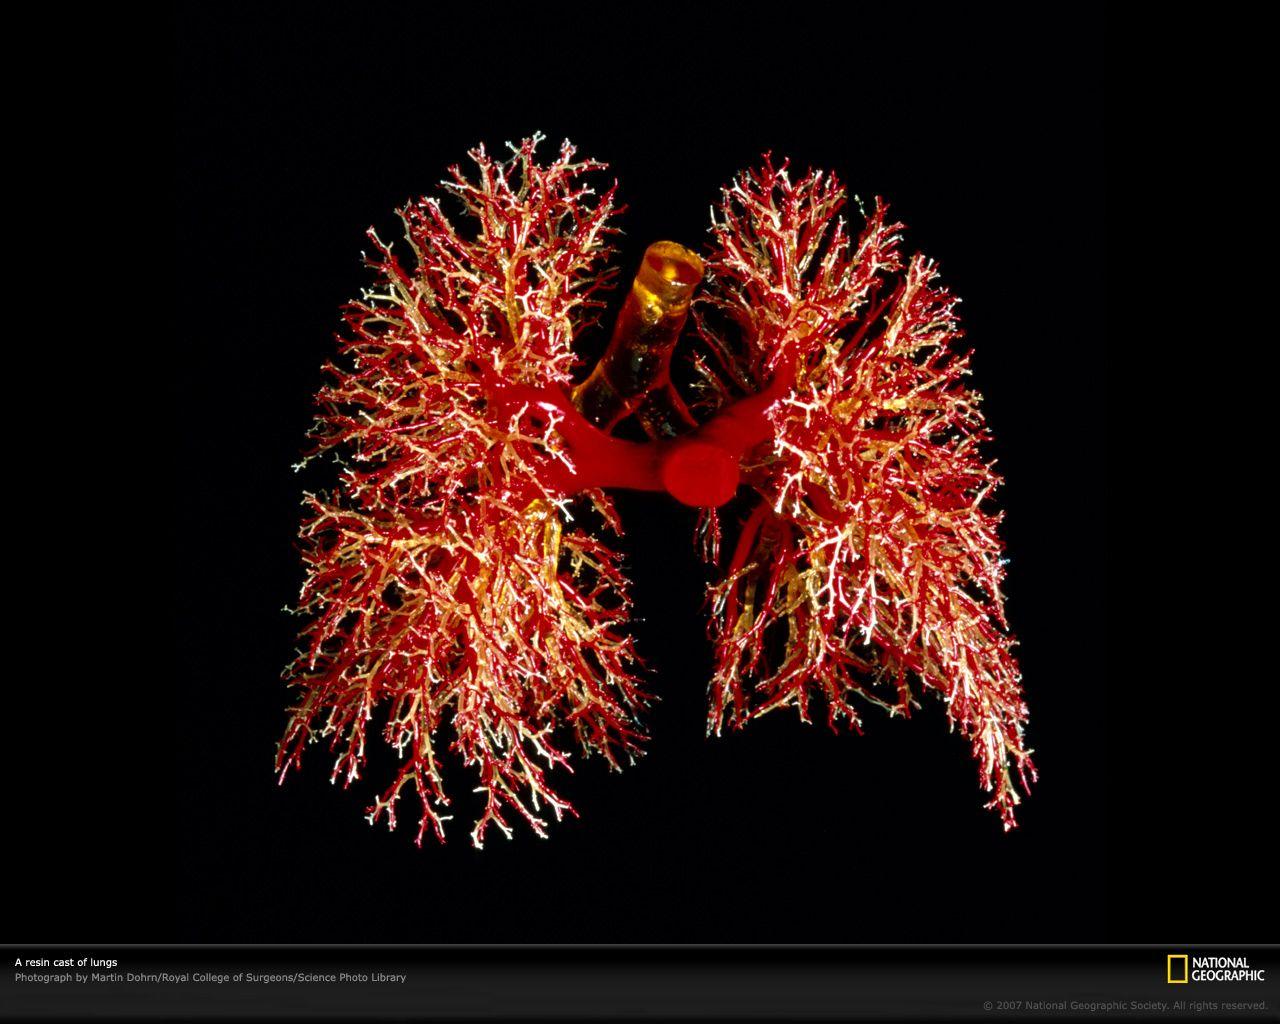

Lungs Wallpapers - Wallpaper Cave

wallpapercave.comlungs disease

wallpapercave.comlungs disease